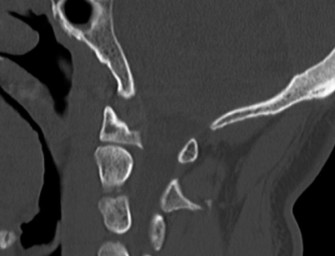

CASE 1 A 63-year-old male sustained a hyperextension injury to his neck while diving into a pool. Upon presentation, he reports decreased sensation in his hands and decreased strength in his arms and wrists, but no lower extremity complaints. On motor examination, he has 5/5 strength in his deltoids and elbow flexors and 4/5 strength in the elbow extensors, wrist extensors, and finger flexors. Lower extremity motor examination is normal. Sensation is decreased to light touch in both hands. Otherwise his sensation is preserved. Images of his cervical spine are shown in Figures 1–1 to 1–3.

Figure 1–2

The correct answer is (B). The clinical scenario describes a patient with central cord syndrome (CCS). CCS continues to be the most common incomplete spinal cord injury accounting for 15.7% to 25% of all spinal cord injuries. The characteristic presentation is an extension moment injury in a previously spondylotic and stenotic spine. Figures 1–1 to 1–3 demonstrate a spondylotic spine with central narrowing and CSF effacement that is worst at the C3–4 level. Bleeding, edema, and/or Wallerian degeneration lead to damage of the lateral corticospinal tract which is the main descending motor tract in the spinal cord. The more central anatomic position of the homunculus to the upper extremities places them at greater risk than those to the lower extremities. As such, injury to the lateral corticospinal tract is characterized by upper more than lower extremity involvement and motor deficits being more pronounced than sensory deficits.